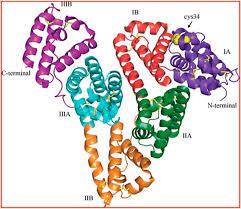

قیمت: 31٬000 تومان - دسته بندی فایل: علوم پزشکیآلبومین سرم انسان 19 صفحه word

فروش ویژه نسخه حرفه ای آلبومین سرم انسان با تخفیف استثنایی فقط 18 هزار تومان تعداد صفحات: 19 صفحه